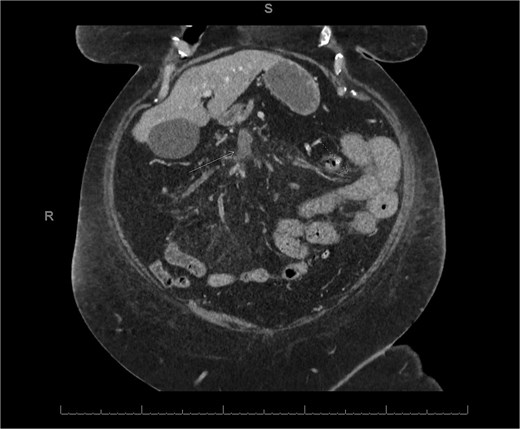

A 76-year-old female with a 3-day history of left upper abdominal pain, vomiting, and haematochezia. Her history included pulmonary embolism, multiple deep vein thromboses, with no ongoing anticoagulation, and an open partial colectomy for complicated diverticulitis a decade earlier. On admission, she was afebrile but tachycardic and showed localized tenderness in the left hypochondrium. Laboratory revealed leucocytosis with a white blood cell count (WBC) of 12 G/L, elevated C-reactive protein (CRP) of 46 mg/L, and hyperlactatemia of 2.6 mmol/l. Enhanced computed tomography (E-CT) revealed jejunal venous ischemia in the left upper quadrant, secondary to extensive porto-mesenteric thrombosis with reduced bowel wall enhancement, distention, and free intraperitoneal fluid (Fig. 1). She was managed conservatively with unfractionated heparin (UFH) with a bolus of 5000 U/l followed by 30 000 U/l/24 h (target INR 0.35–0.7), Piperacillin-Tazobactam, and bowel rest. After 48 h of monitoring in the intensive care unit (ICU), she exhibited marked biological and clinical improvement. E-CT on the third day showed restored bowel wall enhancement and stable porto-mesenteric thrombosis (Fig. 2). She was discharged on therapeutic low molecular weight heparin (LMWH) with enoxaparin sodium 120 mg every 12 h. At the 3-month follow-up, E-CT revealed near-complete thrombus resolution, without intestinal sequelae (Fig. 3).

Follow-up E-CT 72 h after conservative management in the first patient. Dashed arrows show improved viability of the small bowel with bowel wall enhancement. White arrows revealed the stability of the extended porto-mesenteric thrombosis.